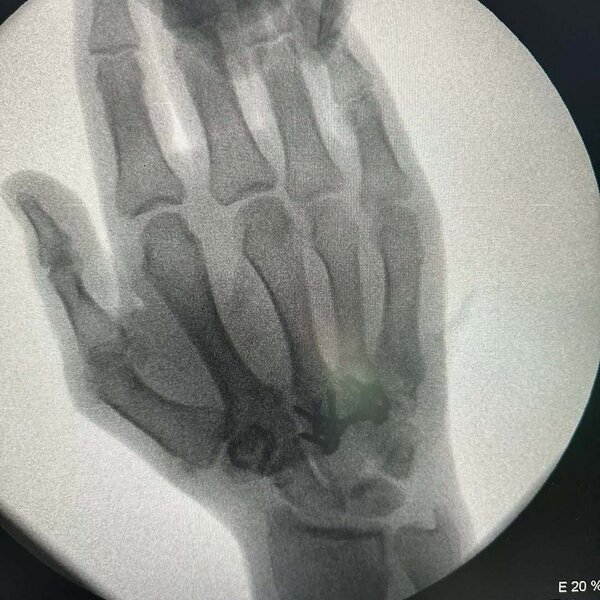

Tanınmış idmançı, karateçi Rafael Ağayev yenidən əməliyyat masasına keçib.

Ölkə.Az xəbər verir ki, R.Ağayevin əlinin üç sümüyü sınıb.

1 həftədə ikinci dəfə xəstəxanaya müraciət edildiyi deyilən Rafael Ağayevin bir gündə iki əməliyyat keçirdiyi məlum olub.